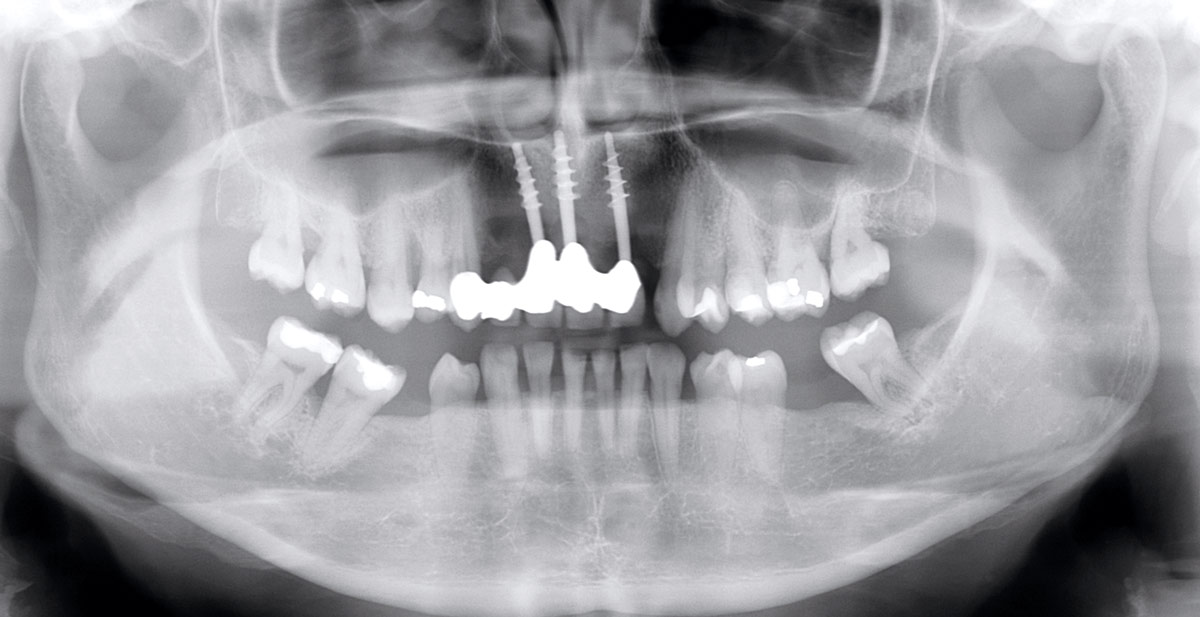

16/17 - X-ray scan after uncovering the implantsRestoration of all four incisors with maxgraft® bonebuilder - Dr. Dr. Dr. O. Blume